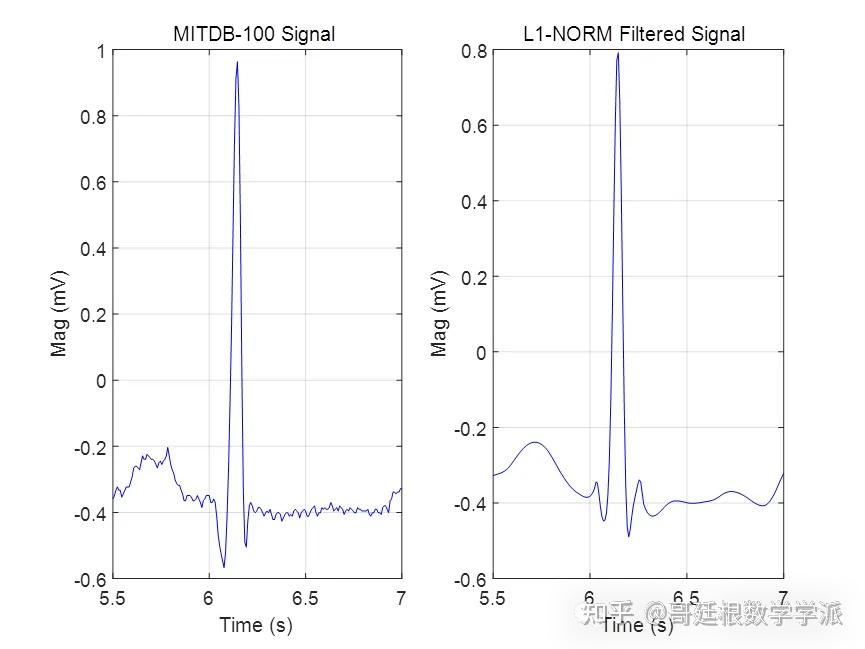

基于L1范数惩罚的稀疏正则化最小二乘心电信号降噪方法(Matlab R2021B)